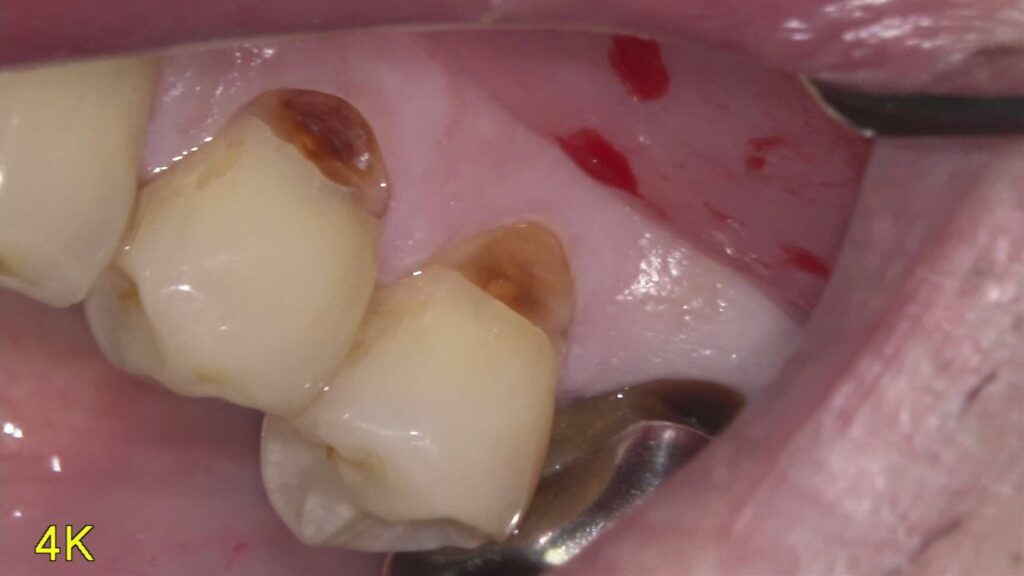

左下2・3・4番の虫歯を即日CRで治療しました【保険診療】

「虫歯を治したい」という主訴でご来院されました。診査の結果、左下2・3・4番に虫歯が確認できたため、即日でコンポジット…